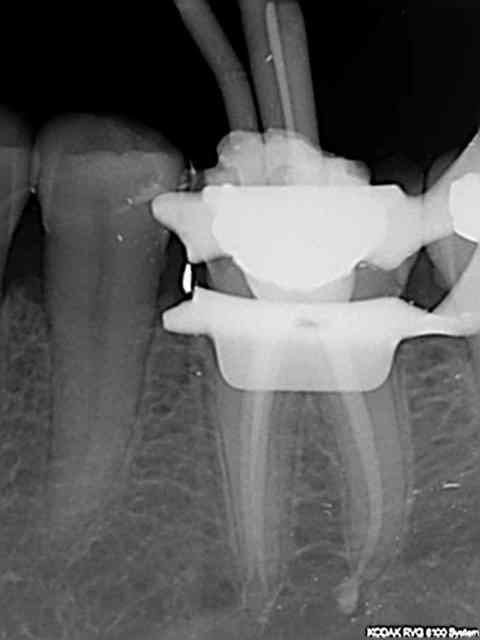

26, 60 mn endo molaire dont 30 pour trouver le canal DV (chambre calcifiée). J'ai failli jeter l'éponge mais le sx a fini par s'engager. Grosse frayeur toutefois avec le s1 sur endomaster car il a bipé d'ès son entrée dans le canal, mais c'était du à un excès d'irrigant. Ouf !

36, 30 mn endo molaire, vitesse de croisière retrouvée !))))